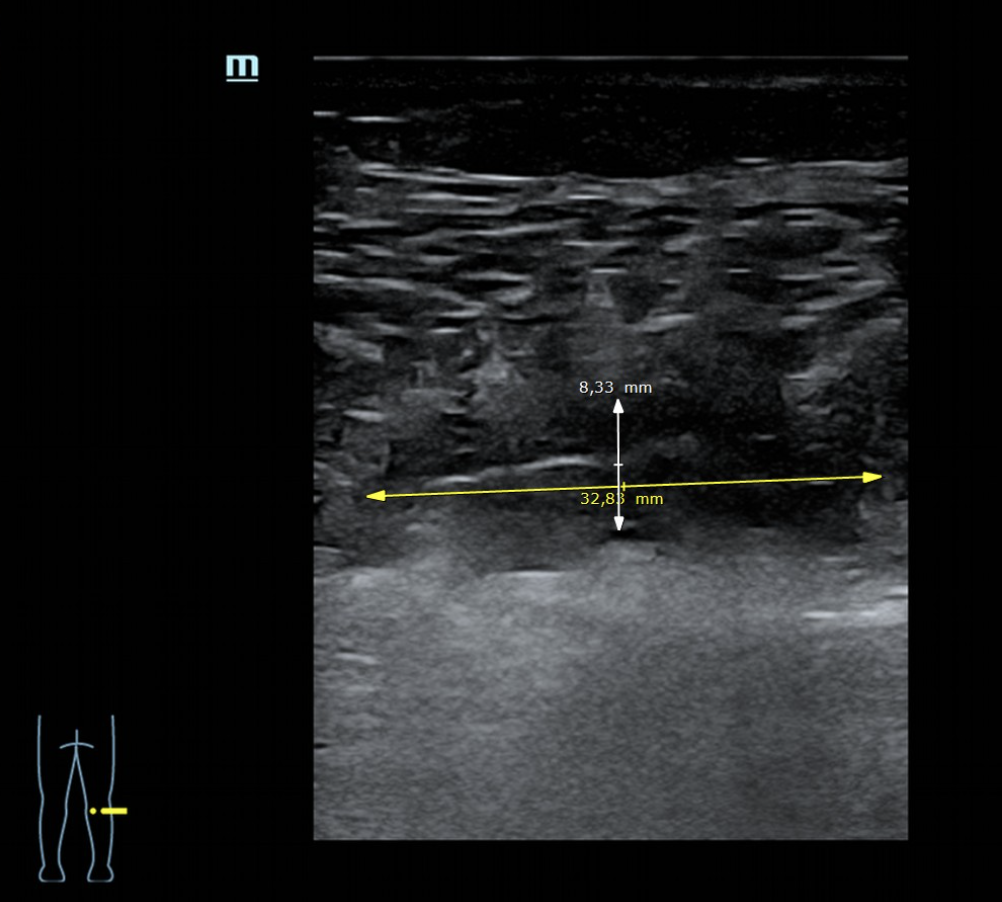

La ecografía, realizada con sonda de alta frecuencia sobre la cara medial e interna del gemelo, muestra una disrupción fibrilar con un defecto de 32,9 mm en su eje mayor y 8,3 mm en el menor. Se aprecia pérdida de la arquitectura normal con áreas hipo e hiperecogénicas compatibles con sangrado, edema y retracción de los extremos de la rotura. Se descarta TVP en eje poplíteo.

El diagnóstico final es rotura fibrilar del gemelo medial secundaria a sobreesfuerzo. La TVP constituye el principal diagnóstico diferencial en un cuadro de dolor agudo de pantorrilla con hematoma, especialmente en pacientes con antecedentes venosos relevantes.